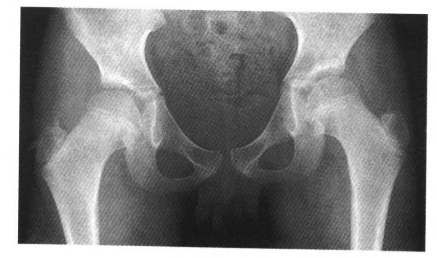

1.股骨头圆韧带窝在髋关节正位片上表现为股骨顶部小半圆形骨质缺损,在旋转屈曲位时表现为股骨头中心部有小空洞(图1)。

图1 正常股骨头圆韧带窝A.韧带窝明显,极似骨缺损;B.转动体位后骨质正常